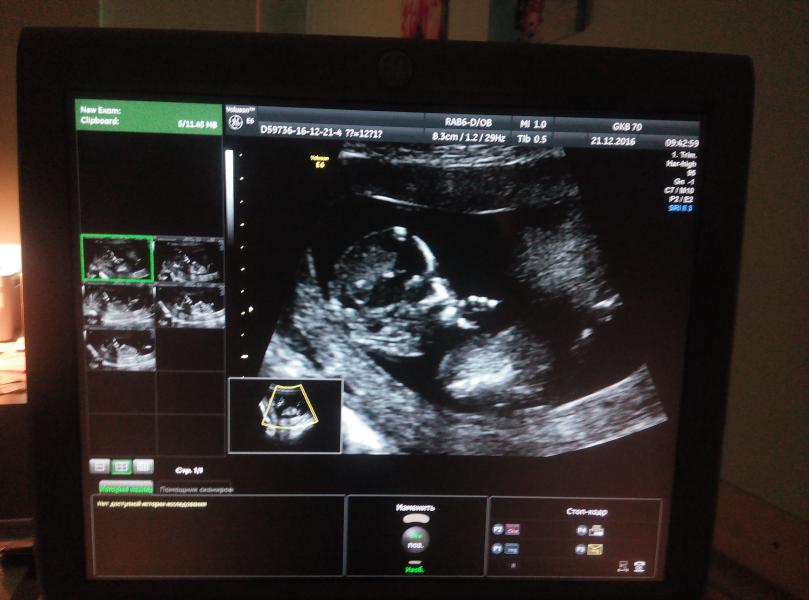

Вчера была на первом скрининге. все посмотрели, пальчики врач посчитала и все- все у малыша хорошо, все соответствует сроку🙏 осталось дождаться результатов крови. Единственное плацента низко и перекрывает внутренний зев 😔 буду ждать пока поднимется. И еще, предположили принцессу в животике👸 ,если ничего не "отрастет", будет наш папа в малиннике жить 😊